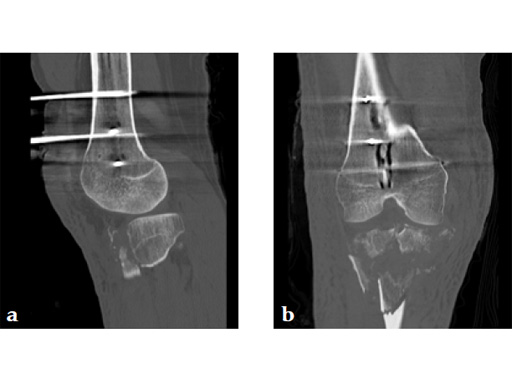

A 36-year-old man sustained a motorcycle injury: right femoral shaft fracture and right hyperextension bicondylar tibial plateau variant (Fig 1, Fig 2).

Staged management with initial rodding of femur and placement of spanning knee external fixator with closed manipulative reduction of tibial plateau (Fig 3).